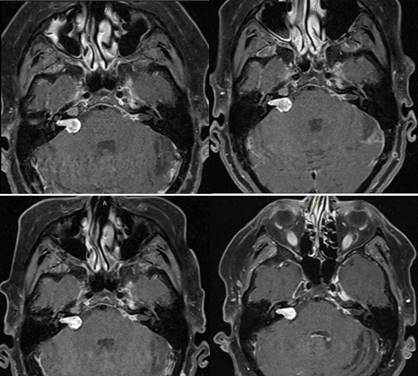

El seguimiento de la paciente fue clínico e imagenológico. Se realizaron RNM de cráneo cada 6 meses luego de RC. Figura 6. Nótese en la primera y segunda RM se observa la lesión con centro hipodenso en relación a los cambios pos RC. El tamaño tumoral se ha mantenido incambiado en los estudios realizados.

Figura 6: Secuencia cronológica de controles con RNM pos RC. Se pueden observar los cortes axiales en la secuencia T1 con contraste. De izquierda a derecha y de arriba abajo octubre 2019, marzo 2020, octubre 2020 y abril 2021.